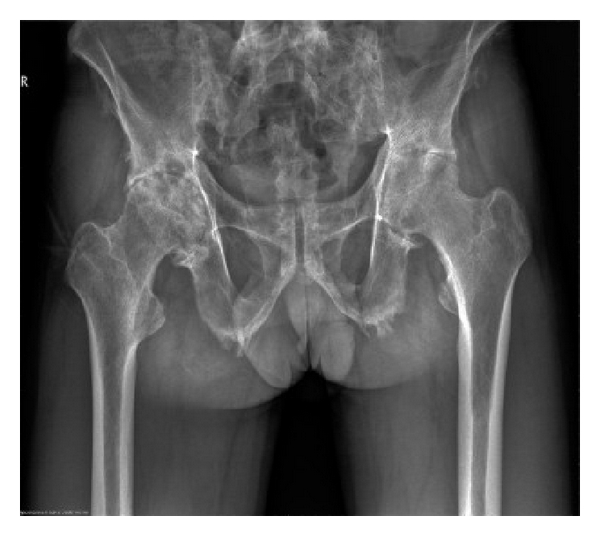

Preoperative characteristics of patients are listed in Table 1. The mean age and disease duration of patients were 37.1 ± 9.0 years (range: 24–52 years) and 13.7 ± 12.4 years (range: 2–40 years), respectively. HLA-B27 was positive in all patients. RF and ANA were negative. No patient had a history of iritis. Five patients had elevated ESR (5/7, 71.4%). Six patients had increased CRP (6/7, 85.7%). Radiographic evaluation of hips showed narrowed joint spaces ranging from 0 to 7 mm, including 3 of 7 patients with complete disappearance of the joint space (Figure 1). Serum levels of IgG and IgG4 were not measured.

(a)

(b)

(c)

(d)